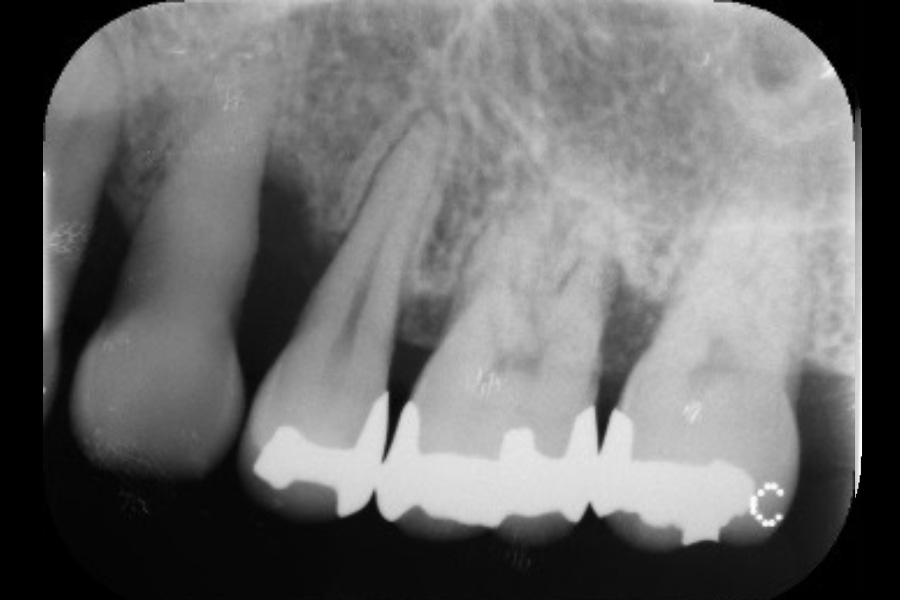

左上奥歯の歯ぐきが腫れて、噛むと痛い

【歯周組織再生療法】

- 担当医

- 清水 宏康先生

- 主訴

- 左上奥歯の歯ぐきが腫れて、噛むと痛い

- 期間

- 再生療法から再評価まで6か月

- 費用

- ¥220,000(税込)

- 治療内容

- 左上4遠心と左上6近心に垂直性骨吸収が認められたためエムドゲインと骨補填材を用いて歯周組織再生療法を行った

- 治療に伴うリスク

- 歯肉退縮、知覚過敏